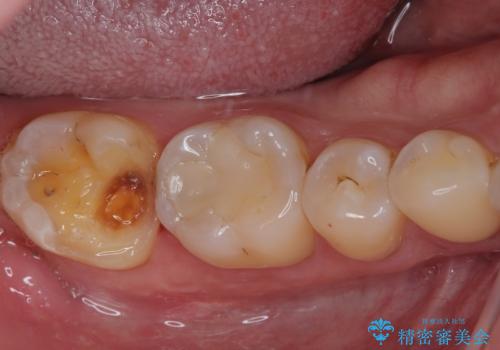

- 右下奥歯に違和感を感じるとのことで来院された患者様です。

食事の際に奥歯に痛みを感じることがあるものの、どの歯であるのかが特定できないとのことでした。

咬合時の痛みは、下顎のみでなく、上顎に原因がある場合もあり、更には頬の筋肉の痛みが原因で歯に痛みを感じることもあるため、診断を慎重に行う必要があります。

頬の筋肉の痛みではないことと上顎の歯に問題がないことは確認ができましたが、下顎の最後臼歯か手前の歯であるかの診断は、非常に難しいものとなりました。

レントゲンやCTでは手前の歯の方が疑わしいように思えましたが、冷熱や電気刺激の反応から正常と判断されました。

最後の確認方法として、局所麻酔を行わずに最後臼歯の銀歯を外し、神経組織近くまで歯質を切削したところ痛みなどを全く感じず、その後無菌的環境下にて切削を進めたところ、神経組織の一部が壊死していることが確認されました。

その後は速やかに根管治療を行い、初回の処置以降は痛みや違和感が一気に引いたため、根管治療後にオールセラミッククラウンにて補綴治療を行うこととしました。